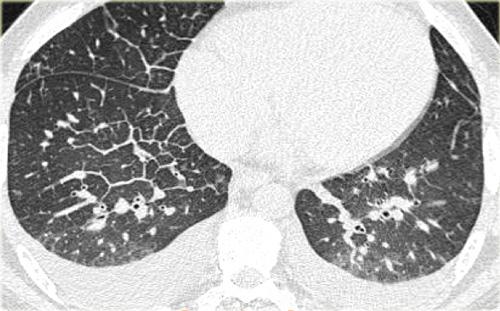

Hình bên trái minh họa các đặc điểm điển hình của phù phổi do tim.

Có hình ảnh dày vách liên tiểu thùy đều đặn và một số vùng mờ dạng kính mờ ở phần thấp của phổi.

Ngoài ra, có hình ảnh tràn dịch màng phổi hai bên.

Hình bên trái là một ví dụ khác về phù phổi do tim.

Bệnh nhân này được chụp CT để loại trừ thuyên tắc phổi.

Có hình ảnh dày vách liên tiểu thùy đều đặn và mờ dạng kính mờ với phân bố dạng đốm không đều.

Lưu ý: phù phổi có thể có hình ảnh rất không điển hình và phân bố rất không đồng đều — một số vùng bị lấp đầy dịch trong khi các vùng lân cận ngay bên cạnh lại có hình ảnh hoàn toàn bình thường.